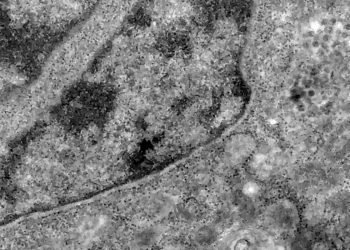

Tag: células